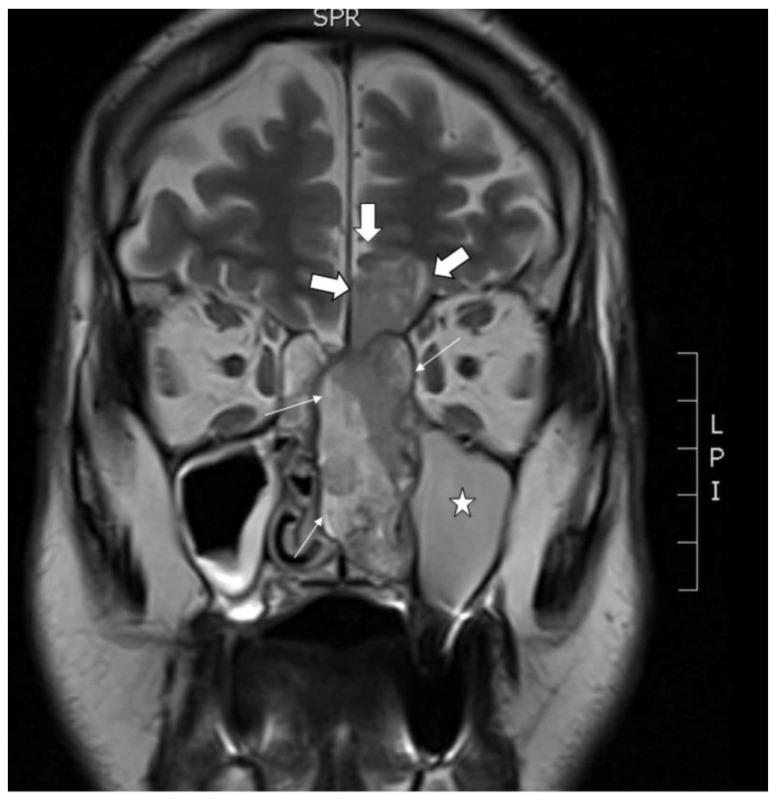

Sinonasal teratocarcinosarcoma (TCS) is a rare tumor that displays a variable histology with admixtures of epithelial, mesenchymal, neuroendocrine and germ cell elements. Facing a very poor prognosis, patients with TCS are in need of new options for treatment. Recently identified recurrent mutations in may serve as target for modern therapies with EZH1/2 and CDK4/6 inhibitors. Here, we present the first in vitro cell line TCS627, established from a previously untreated primary TCS originating in the ethmoid sinus with invasion into the brain. The cultured cells expressed immunohistochemical markers, indicating differentiation of epithelial, neuroepithelial, sarcomatous and teratomatous components. Whole-exome sequencing revealed 99 somatic mutations including , , , , , and , all present both in the primary tumor and in the cell line. Focusing on mutated as the therapeutic target, growth inhibition assays showed a strong response to the CDK4/6 inhibitor palbociclib, but much less to the EZH1/2 inhibitor valemetostat. In conclusion, cell line TCS627 carries both histologic and genetic features characteristic of TCS and is a valuable model for both basic research and preclinical testing of new therapeutic options for treatment of TCS patients.

鼻窦胚胎性横纹肌肉瘤(TCS)是一种罕见的肿瘤,其组织学表现多样,混合有上皮、间叶、神经内分泌和生殖细胞成分。由于预后极差,TCS 患者需要新的治疗选择。最近发现的 中的反复突变可作为 EZH1/2 和 CDK4/6 抑制剂等现代治疗方法的靶点。在这里,我们首次报道了源自未治疗过的原发于筛窦并侵犯大脑的 TCS 的体外细胞系 TCS627。培养的细胞表达免疫组织化学标志物,表明上皮、神经上皮、肉瘤和畸胎瘤成分的分化。全外显子组测序显示 99 个体细胞突变,包括 、 、 、 、 、 和 ,这些突变均存在于原发肿瘤和细胞系中。聚焦于突变的 作为治疗靶点,生长抑制试验显示对 CDK4/6 抑制剂 palbociclib 有强烈的反应,但对 EZH1/2 抑制剂 valemetostat 的反应要小得多。总之,细胞系 TCS627 具有 TCS 的组织学和遗传学特征,是用于 TCS 患者治疗新治疗选择的基础研究和临床前测试的有价值模型。